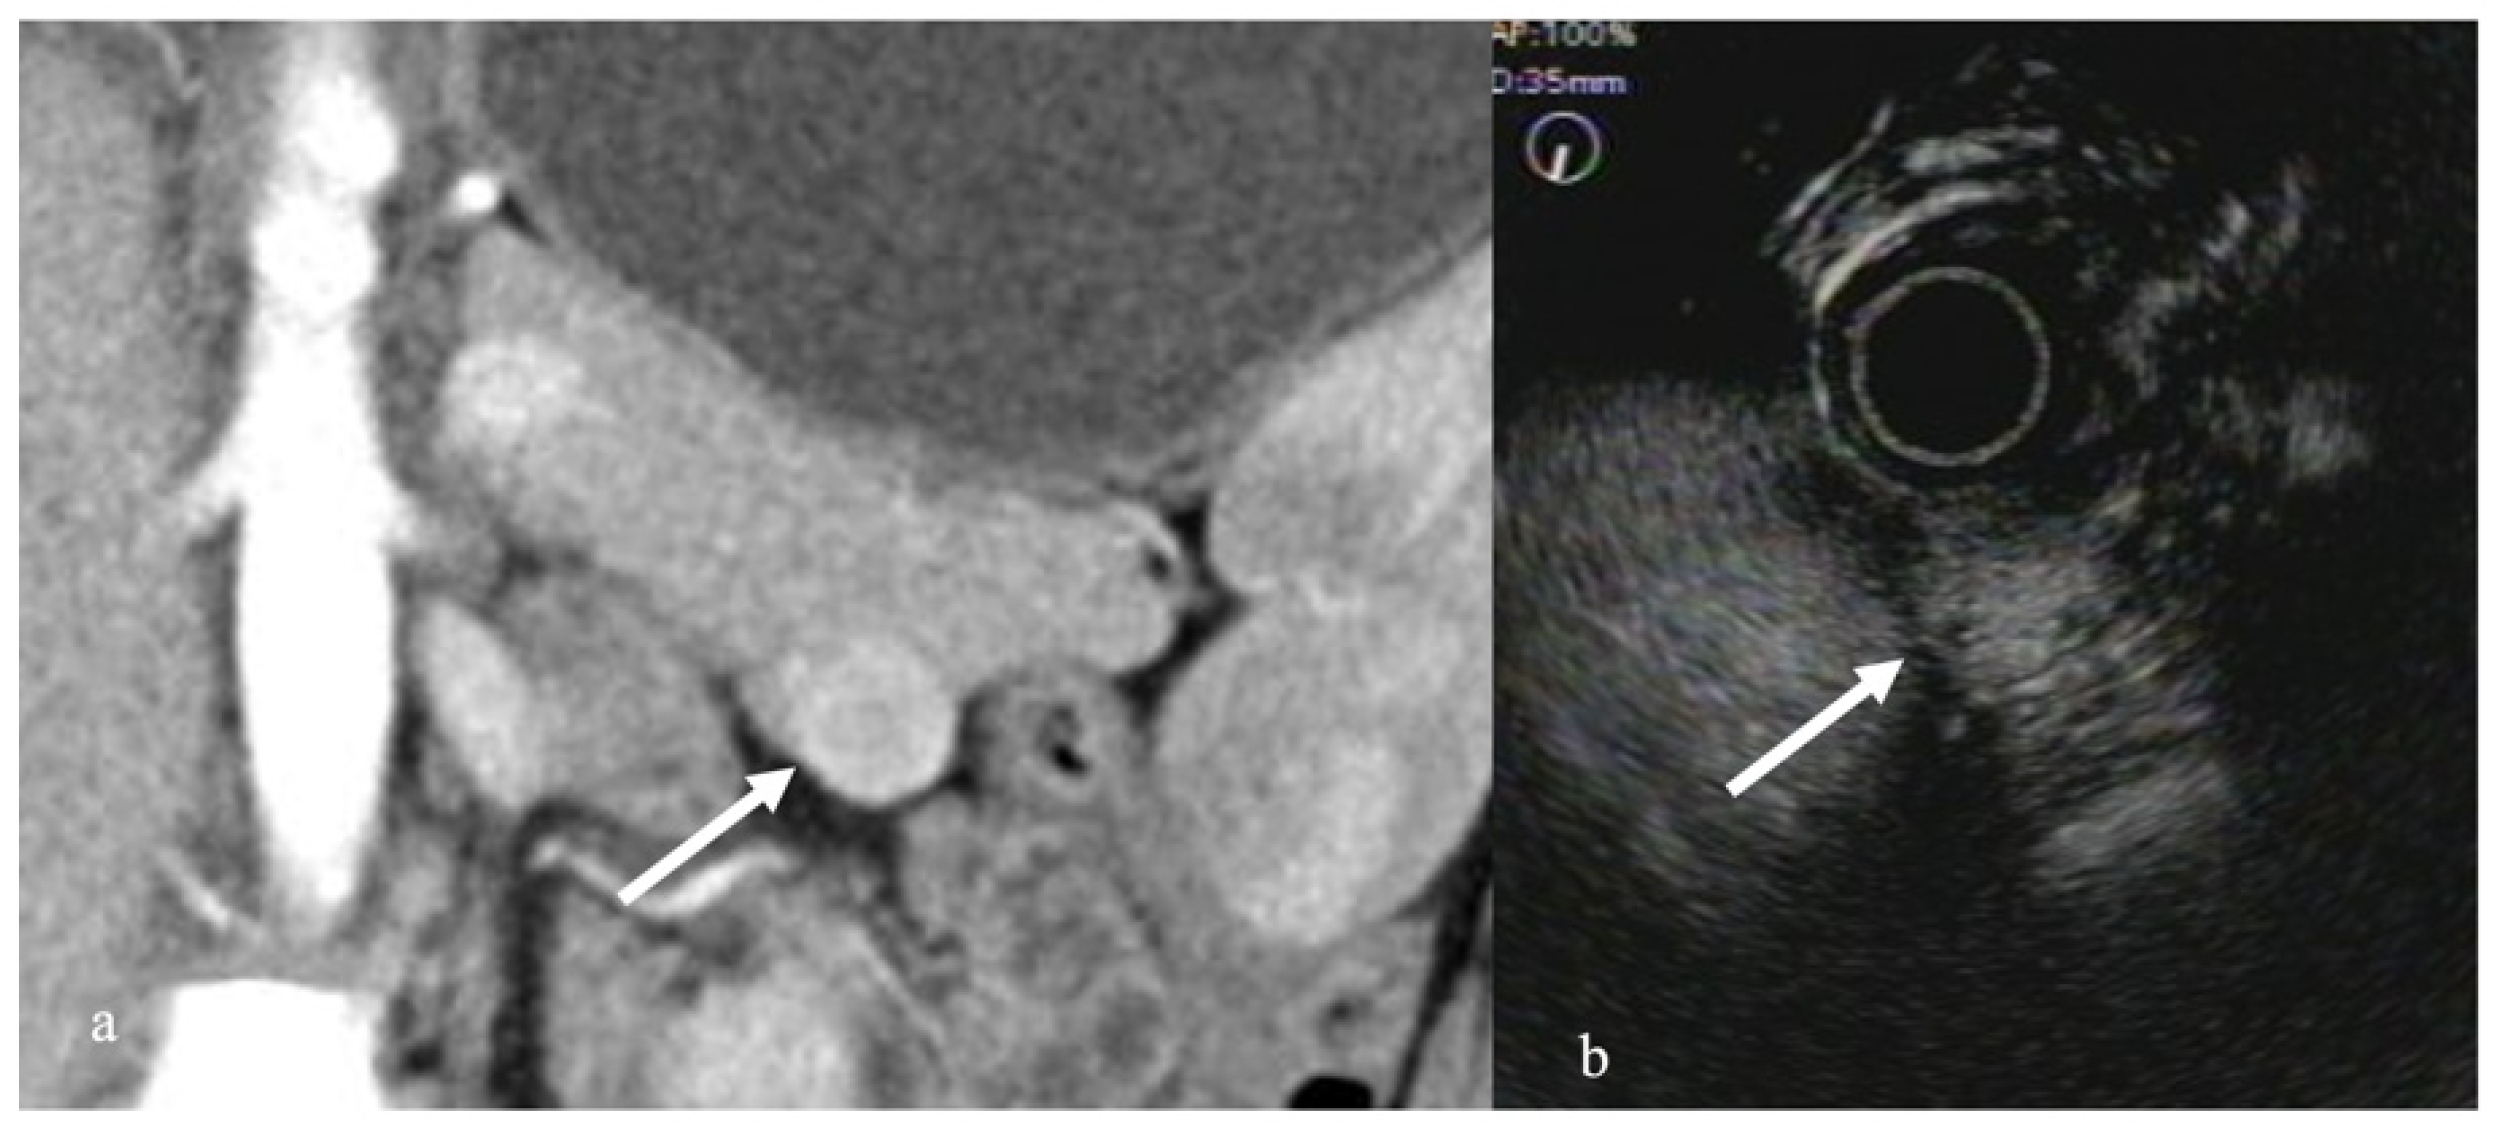

3.2. Autoimmune Pancreatitis

- Hocke, M.; Ignee, A.; Dietrich, C.F. Contrast-enhanced endoscopic ultrasound in the diagnosis of autoimmune pancreatitis. Endoscopy 2011, 43, 163–165. [Google Scholar] [CrossRef]

- Imazu, H.; Kanazawa, K.; Mori, N.; Ikeda, K.; Kakutani, H.; Sumiyama, K.; Hino, S.; Ang, T.L.; Omar, S.; Tajiri, H. Novel quantitative perfusion analysis with contrast-enhanced harmonic EUS for differentiated autoimmune pancreatitis from pancreatic carcinoma. Scand. J. Gastroenterol. 2012, 47, 853–860. [Google Scholar] [CrossRef]

- Kobayashi, G.; Fujita, N.; Noda, Y.; Ito, K.; Horaguchi, J.; Koshida, S.; Kanno, Y.; Ogawa, T.; Masu, K.; Michikawa, Y. Vascular image in autoimmune pancreatitis by contrast-enhanced color-Doppler endoscopic ultrasonography: Comparison with pancreatic cancer. Endosc. Ultrasound 2014, 3 (Suppl. 1), S13. [Google Scholar]